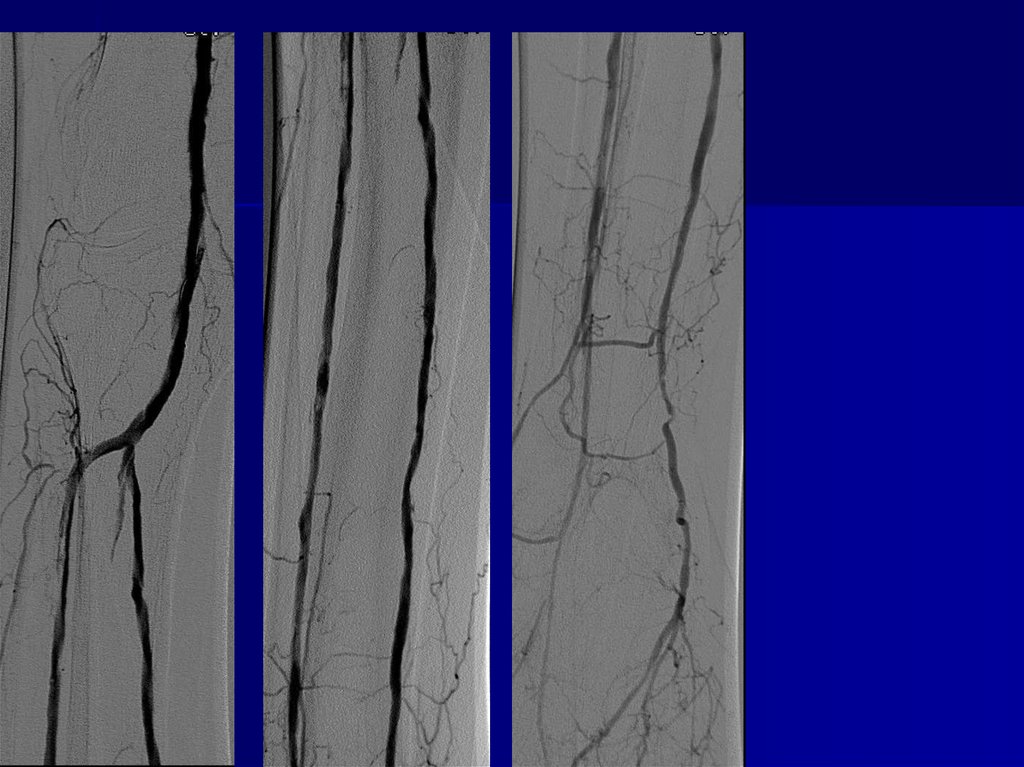

Клинический пример 2

КЛИНИЧЕСКИЙ ПРИМЕР 3

50.